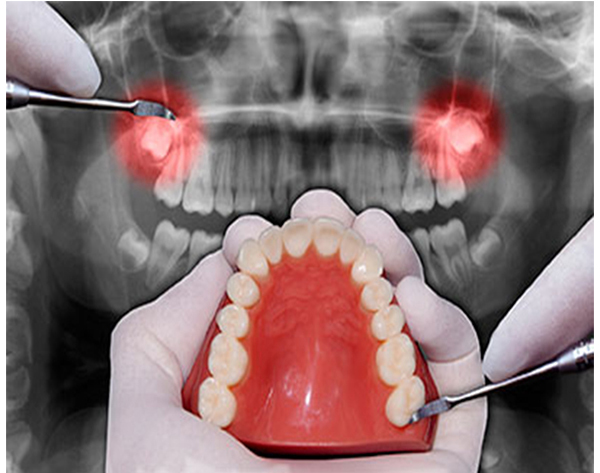

La cirugía oral es llevada a cabo para solucionar problemas en la cavidad oral, como por ejemplo la necesidad de extraer una pieza dental o detectar enfermedades. Dentro de los tipos de cirugías podemos diferenciar varios tratamientos:

- Extracciones de muelas del juicio,